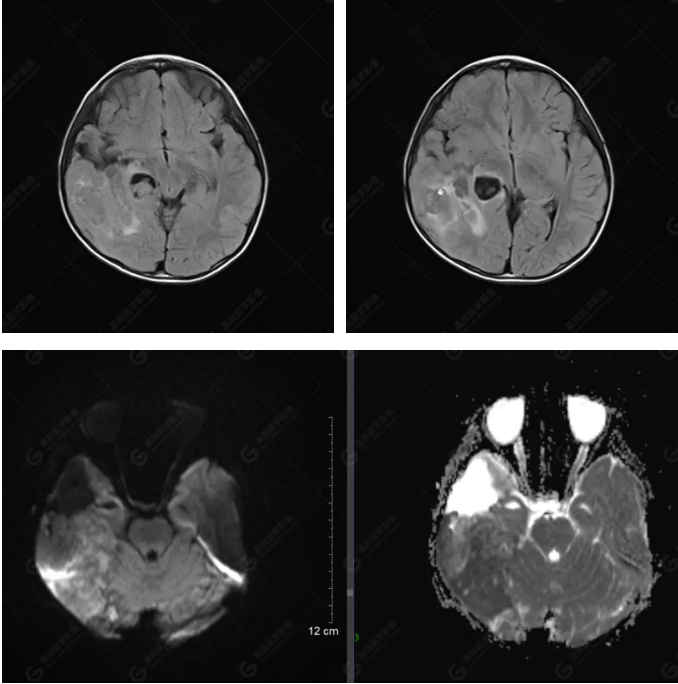

右側(cè)顳葉腫瘤切除術(shù)后(具體不詳):右側(cè)顳部骨質(zhì)不連續(xù)呈術(shù)后改變,右側(cè)顳葉術(shù)區(qū)見片狀長T1長T2信號影,F(xiàn)LAIR呈低信號;術(shù)區(qū)后方右側(cè)顳枕葉見一巨大占位性病變影,邊界欠清,大小約6.2×5.8×4.3cm(前后×左右×上下),信號不均勻,T1WI呈等稍低信號間雜少許高信號,T2WI呈高稍低混雜信號,DWI示部分病灶彌散受限,相應(yīng)ADC圖減低,磁敏感序列見部分呈極低信號,增強掃描可見明顯不均勻強化,鄰近硬腦膜及小腦幕增厚并明顯強化;另延髓右前方及右側(cè)橋小腦角區(qū)見一不規(guī)則形異常信號影,大小約3.2×1.3×3.7cm(左右×前后×上下),呈長T1稍長T2信號,F(xiàn)LAIR呈等信號,DWI未見受限,增強后明顯均勻強化,鄰近腦膜明顯強化。鄰近腦實質(zhì)及右側(cè)顳角明顯受壓;左側(cè)大腦半球未見局灶性信號異常,中線結(jié)構(gòu)稍左移。

右側(cè)顳葉腫瘤切除術(shù)后:現(xiàn)術(shù)區(qū)后方右側(cè)顳枕葉及延髓右前方占位,右側(cè)顳枕部硬腦膜及小腦幕明顯強化,結(jié)合既往影像資料,考慮為胚胎源性惡性腫瘤,如非典型畸胎樣/橫紋肌樣瘤(AT/RT)或原始神經(jīng)外胚層腫瘤(PNET)。